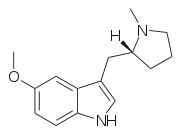

| 5-MeO-pyr-T | artificial | 5-OCH3 | (CH2)4 | 5-Methoxy-3-[2-(pyrrolidin-1-yl)ethyl]-1H-indole | 3949-14-2 | |

5-MeO-MPMI | 5-Methoxy-3-{[(2R)-1-methylpyrrolidin-2-yl]methyl}-1H-indole | 143321-57-7 |